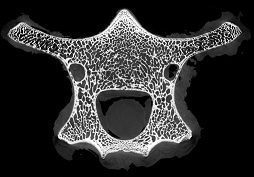

脊椎骨里的“笑臉表情包”

作者:ZZ 日期:2021-07-15 點擊數(shù):14886次

micro CT不僅能夠獲得整體骨量的變化,還能獲得骨骼內(nèi)部骨小梁骨微結(jié)構(gòu)的定量指標(biāo),進而將骨小梁微結(jié)構(gòu)指標(biāo)、皮質(zhì)骨指標(biāo)及骨量結(jié)合起來,綜合評價骨強度和骨量在骨質(zhì)疏松癥發(fā)生和發(fā)展中的作用。